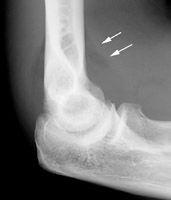

箭頭所指透亮區即為脂肪墊影像,由於關節囊內出血,使關節滑膜,脂肪墊被推移,在側位片上出現象“船帆”狀,或是說“八”字狀影像。

脂肪墊征是指通過前後脂肪墊前後移位證實關節囊內滲出,提示肘關節內的積血、積液改變;雖然肘關節x片中看不到骨折線,但是出現前脂肪墊征時強烈提示有橈骨小頭骨折。